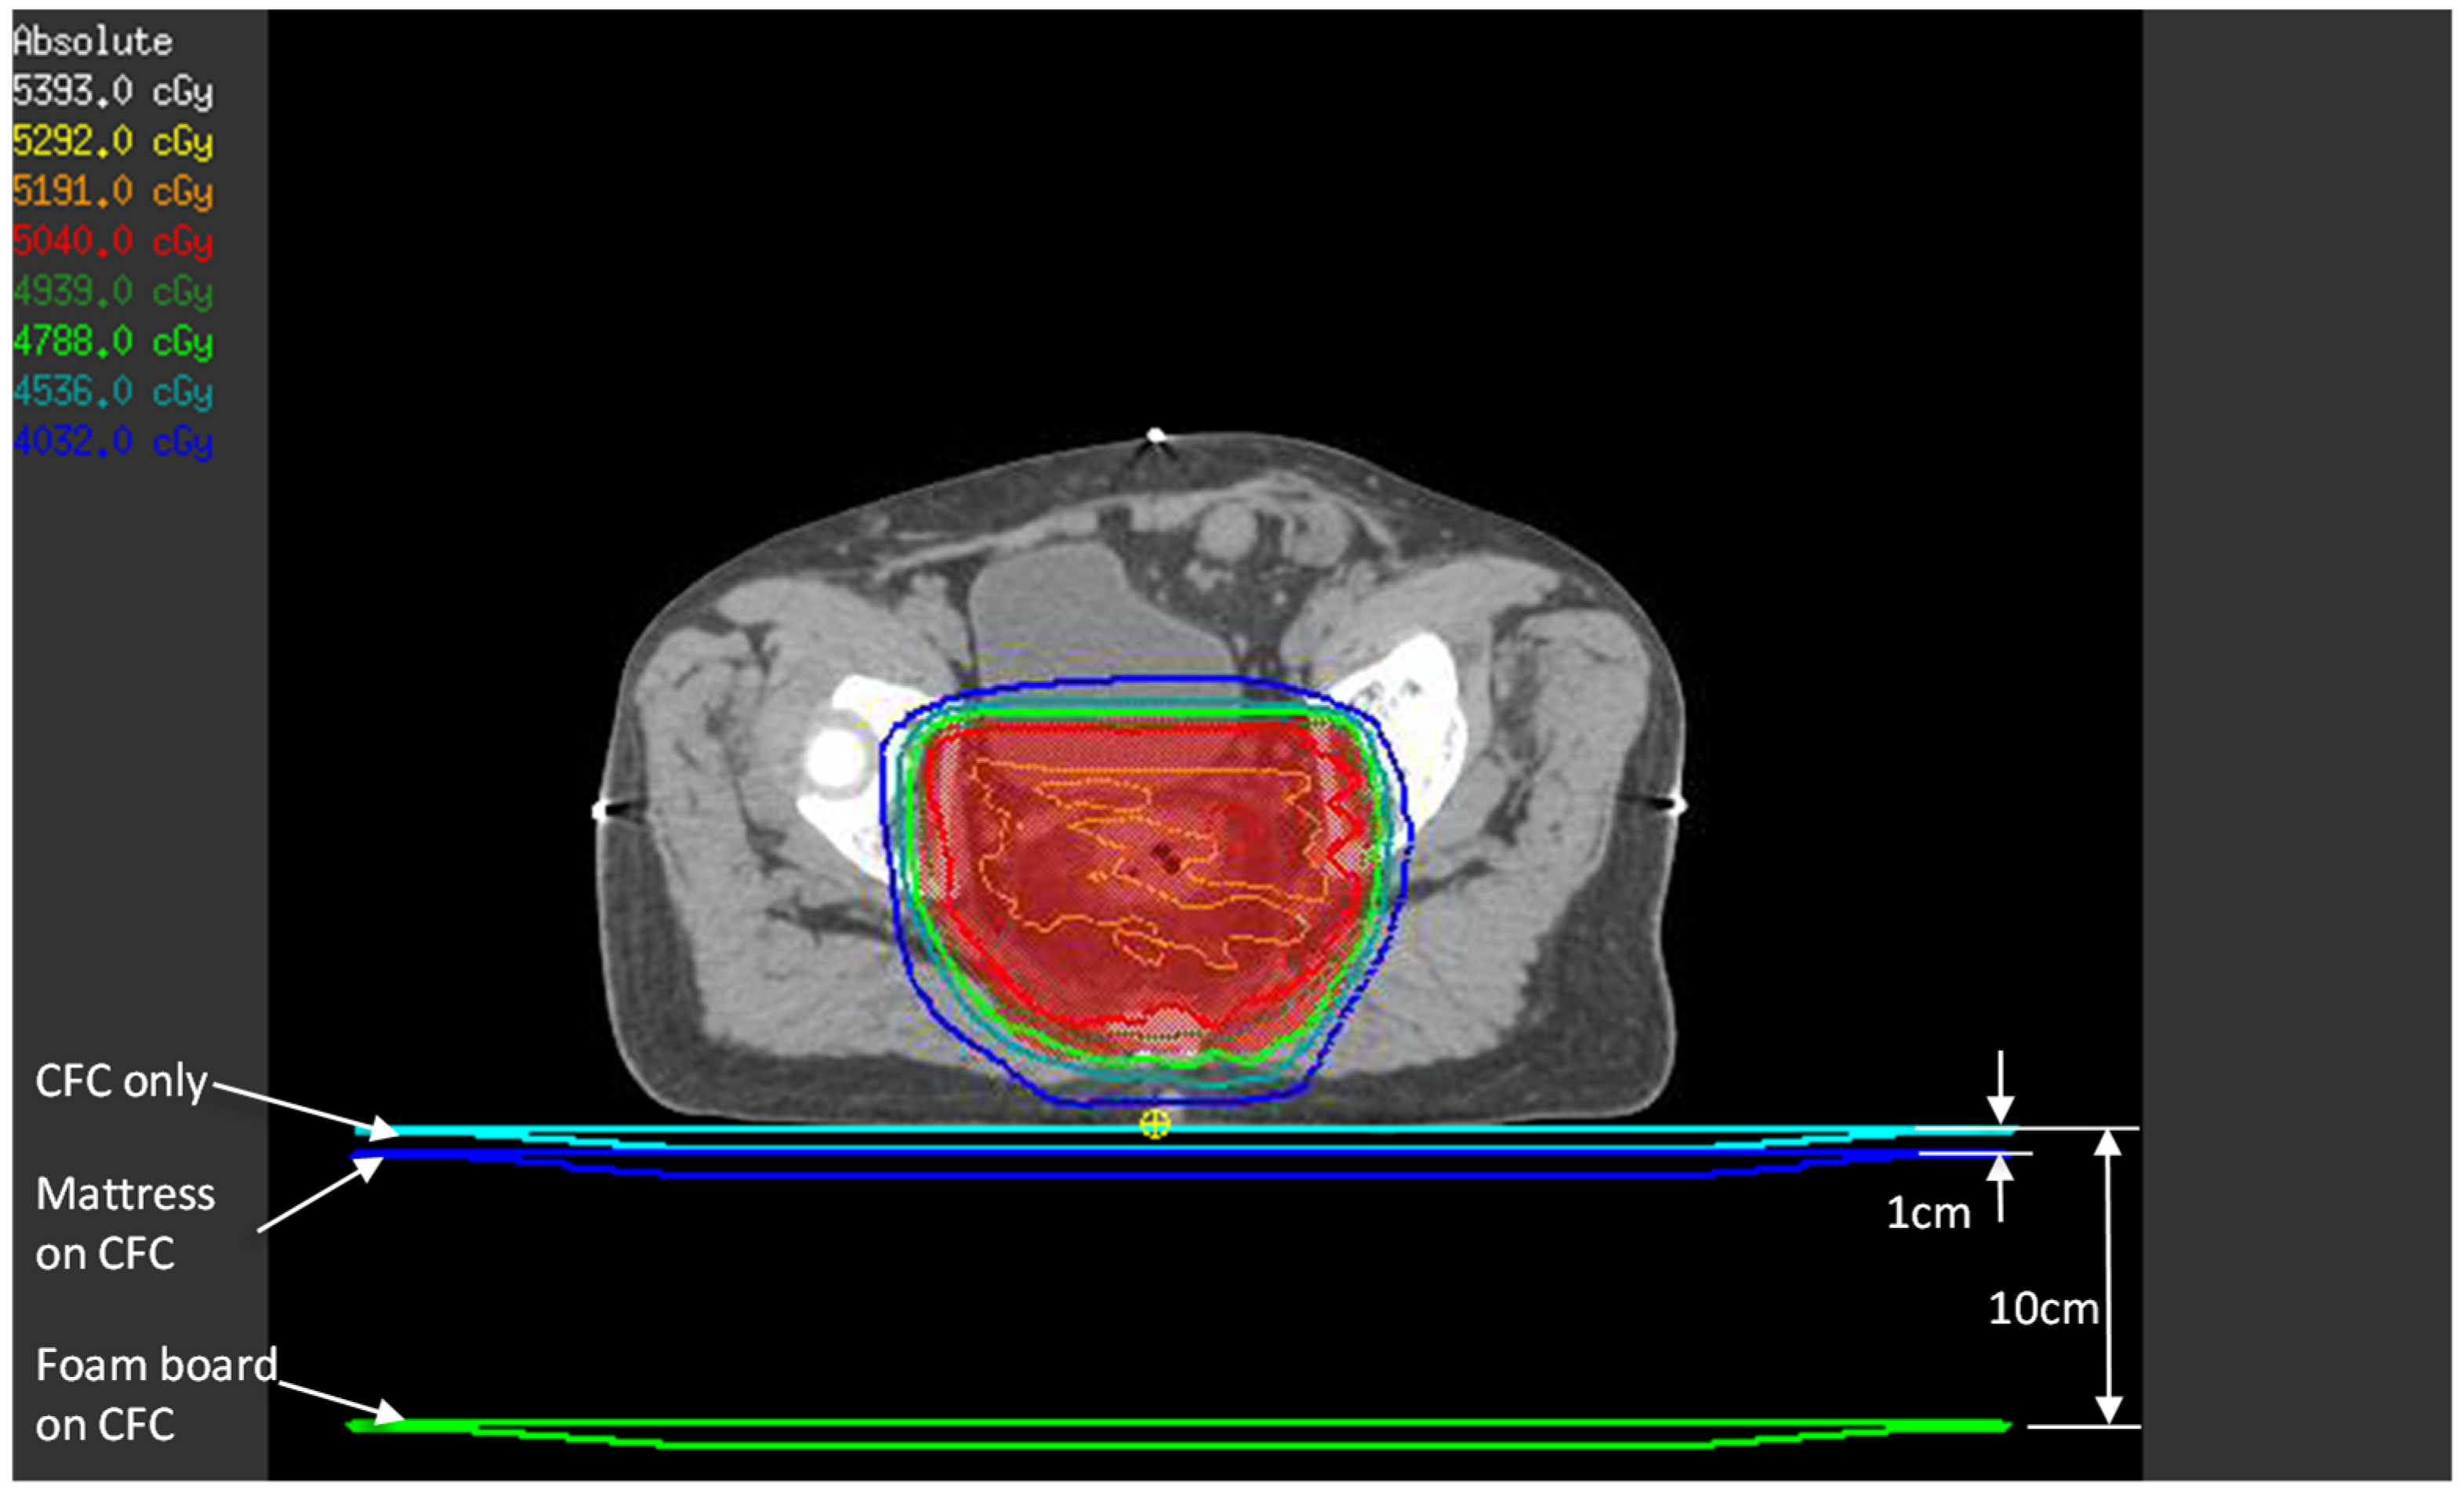

Although TPS estimation of the surface and buildup doses has accuracy issues when using a collapsed cone convolution algorithm [18], we thought it would be instructive to compare TPS calculations and the OSLD phantom measurements. The patients’ treatment CT images and VMAT plans were used in this estimation. To simulate the effect of each setup, the 1 cm water-equivalent couch model that we use clinically was placed directly under the patient (simulates CFC only setup), 1 cm from the posterior of the patient (simulates mattress setup), and 10 cm from the patient’s posterior surface (simulates foam board setup), as in Figure 3. A dose point was created at 1.2 mm depth from the patient’s posterior surface immediately below the beam isocenter—this represents the approximate location of the OSLD sensitive volume in the phantom experiment.

Figure 3.

TPS estimate of posterior skin dose with the three setups. For each setup (CFC only, mattress, and foam board), the three couch models shown were density-overridden to 1 g/cm3 one at a time, and beams were calculated to obtain the posterior skin dose, represented by the small yellow point of interest.

In the Pinnacle3 TPS, creating a region of interest to represent the mattress or the foam board and density-overriding it does not factor into the dose calculation. The TPS treats these as “air”, since the mattress and the foam board have a much lower density than the threshold density above which the dose calculation algorithm acts upon (we set this threshold to 0.6 g/cm3). Hence, the method described above is the closest approximation to the three setups in this study.